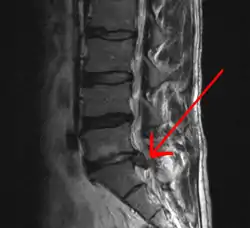

Звужений простір між L5 і S1 хребцями, з зазначенням можливої кили міжхребцевого диска - класична картину.

МРТ великих гриж (праворуч) диска L4-L5.